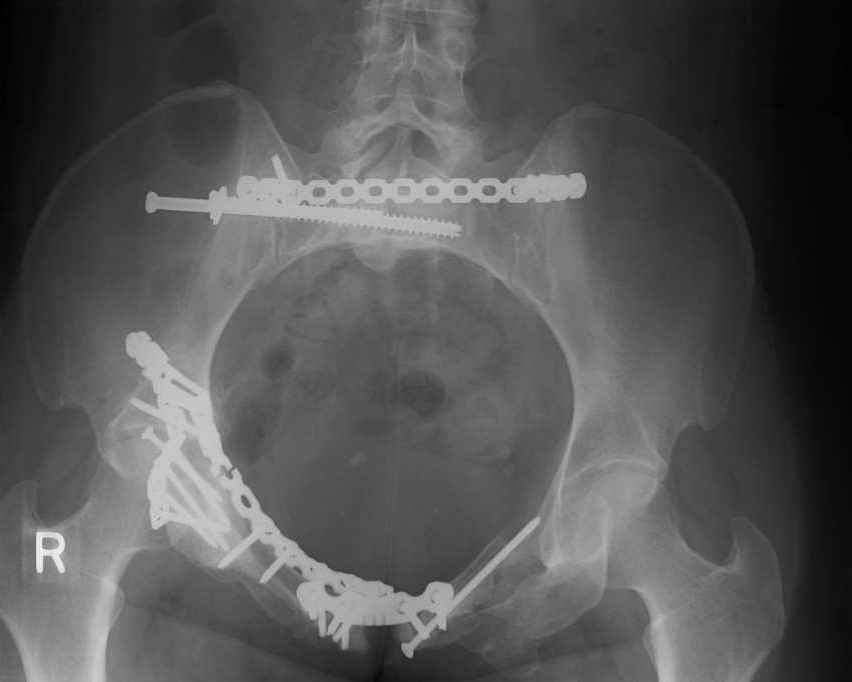

Looking for advice. This is a 48 yo non-smoking female s/p MCC 10 months ago. I do not have the initial injury films. She underwent ORIF as shown on attached file. She is having continued pain in low back/sacral region. Worse with sitting and prolonged walking. Has had pain since surgery. All of her wounds have healed uneventfully. Also has right hip pain laterally. No groin pain. Not aggravated with ROM of the hip. Infection work-up has been negative.

Any thoughts on the broken plate on the pelvic brim and the non-union on the anterior column. Doesn't seem like she's have pain from there.

Maybe remove the disengaged iliosacral screw first to see if she improves?

Thank you...it might help to remove the disengaged and other iliosacral screws then insert longer lag screws into the upper sacral segment and if anatomically feasible into the second sacral segment as well.

At this point, I'd ignore the right pubic root issue if asymptomatic.

If simple measures such as those above fail, then you could remove it all, take down the sacral fracture site, refix with alternate techniques, and bone graft.